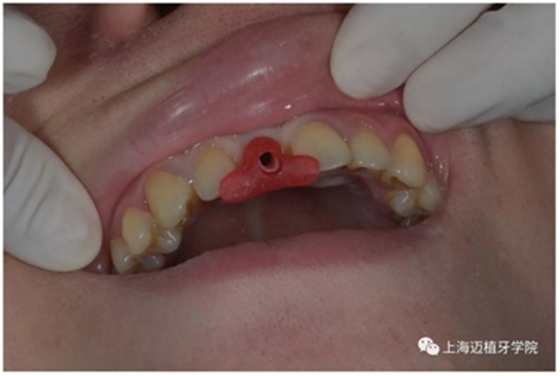

去除愈合基臺:

口內(nèi)個性化基臺: